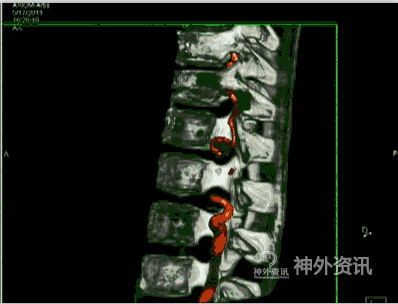

脊髓静脉造影

适应症对临床怀疑脊髓血管疾病或MRIT1像冠状位在中轴线上发现迂曲扩张血管影像,或T2像发现流空血管影;MRIT1像矢状位脊髓背侧呈点状或虫蚀样高信号血管影,或T2像点壮或虫蚀样流空信号影,而规范的选择性脊髓动脉造影又无异常发现时,应行脊髓静脉造影,千方百计寻找有无因椎旁静脉狭窄或闭塞病变引起的脊髓静脉高压综合征,导致脊髓功能损害(图12)。

③经股静脉穿刺插管进入上腔静脉、下腔静脉,分别将造影导管超选择逆行插入奇静脉、半奇静脉、副奇静脉与腰1~4橫静脉[9],注入非离子造影剂(5ml/s、总剂量7ml),了解这些静脉有无向下腔静脉回流障碍,导致脊髓静脉高压综合征。如这些静脉有狭窄、闭塞,或造影剂不能向上、下腔静脉回流时,就返流经椎管内静脉回流至脊髓表面正常引流静脉,引起脊髓静脉高压综合征,导致脊髓功能受损(图14)。

图14: 第三腰横静脉狭窄致脊髓静脉高压综合征A~C. MRI,红色↑示血管流空影;D、E. 第三腰横静脉造影,红色↑示左第三腰横静脉狭窄,绿色↑示向下腔静脉回流少,蓝色↑示向脊髓静脉回流;F. 球囊扩张治疗第三腰横静脉狭窄致脊髓静脉高压综合征,黄色↑示扩张球囊;G. 球囊扩张后,黑色↑示狭窄腰横静脉向下腔静脉回流通畅。